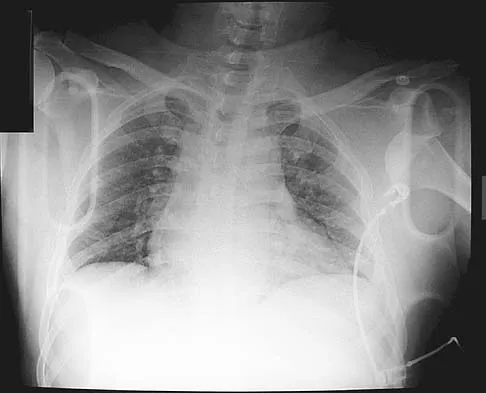

A 39-year-old man has had a foot mass for the past several months. MRI scans are shown in Figures 78a through 78c. A core biopsy specimen reveals synovial sarcoma, and a staging chest CT scan is normal. Which of the following treatments offers the best local tumor control and expedites the patient's return to normal function?

Explanation